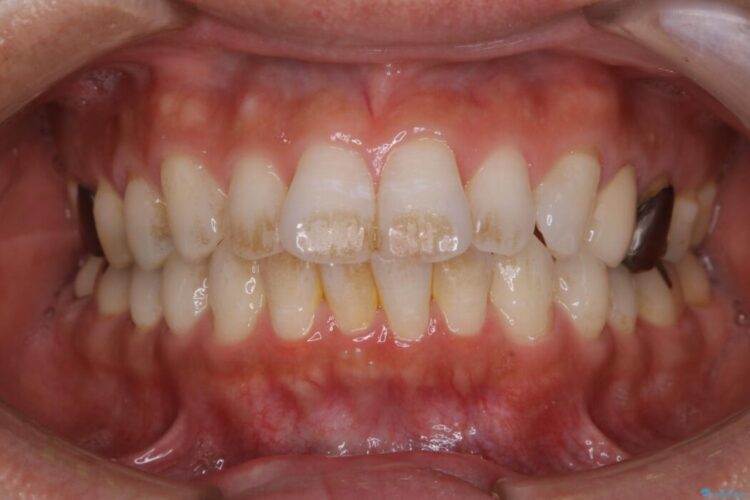

【30代男性】衝撃的なビフォーアフター!クリーニングで見違えるほどの白い歯に

【30代男性】衝撃的なビフォーアフター!クリーニングで見違えるほどの白い歯に ビフォー 【30代男性】衝撃的なビフォーアフター!クリーニングで見違えるほどの白い歯に アフター

歯の着色を綺麗にしたいとご来院されました。